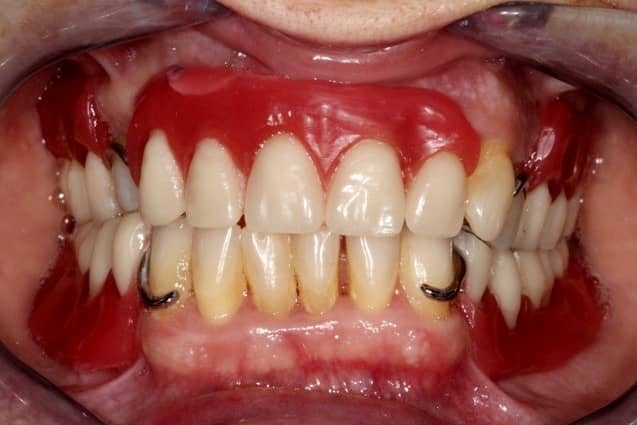

Hölgypáciensünk azzal a panasszal érkezett dr. Sápi Béla kollégánkhoz, hogy pár hónapja több fogát is el kellett távolítani, és azóta sem funkcionálisan, sem esztétikailag nincs kibékülve fogai állapotával.

kapcsos részleges lemezes fogpótlás előtt

Ezek az öntött kapcsok a pótlás viselésekor sajnos nem túl esztétikusak, ám van, amikor eme hátrány ellenére is ez a fogpótlás jelenti a megoldást. Páciensünk mindenesetre maradéktalanul elégedett volt megújult mosolyával!

Kapcsos részleges lemezes fogpótlás után